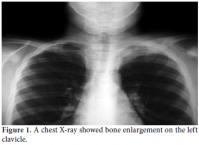

A 10-year-old boy was referred to the Pediatric Rheumatology Unit at the University Hospital Federal University of Pernambuco, Recife in 2008 with a fiveyear history of intermittent pain in his left clavicle, right hip, ankles, and dorsal spine. In 2006, he was admitted to the Pediatric Unit complaining of back pain, fever, and a mass over his left clavicle. Blood tests showed a C-reactive protein (CRP) level of 24 mg/dl and an erythrocyte sedimentation rate (ESR) of 39 mm/h. A chest X-ray confirmed the mass over his left clavicle (Figure 1). Septic osteomyelitis was diagnosed, although his blood and bone cultures were negative. A course of an empirical antibiotic (cephalothin) and NSAIDs was prescribed. He was later referred (after one year) to the Orthopedic Unit where a thoracic computed tomography (CT) scan showed the volume of the left clavicle had increased due to an area of hyperostosis mixed with osteolysis. Hence, the antibiotic was changed to ciprofloxacin for three months. As there was no improvement, he was referred to the Pediatric Rheumatology Unit, where a tuberculin test and ANA were negative. A bone scan showed an increased technetium-99m (99mTc) radioisotope uptake at the left clavicle, ankle, sacroiliac joints, and T8 thoracic disc (Figure 2). Magnetic resonance imaging (MRI) demonstrated multiple inflammatory lesions between the T7 and T9 disks (Figure 3) and in the left clavicle and left ankle (Figure 4), thus confirming the findings on the bone scan and thorax CT. The results of the histological analysis of a bone biopsy were compatible with aseptic chronic osteomyelitis (Figure 5). No infection was identified by lesion or blood culture, and no malignancy was detected by imaging; hence, the possibility of CRMO was raised. An aggressive treatment with NSAIDs, alendronate 70 mg/week, methotrexate 15 mg/week, and infliximab 5 mg/kg was initiated due to the severity of the case and the delay in diagnosis. After the third infusion of infliximab, the boy became free of pain. His ESR and CRP levels were normal, and a bone scan showed a tiny uptake at the left clavicle. It should be noted that the patient and his family gave their consent for any treatment provided at the Pediatric Rheumatology Unit.

An X-ray can show areas of osteolysis at the metaphysis and diaphysis as well as the sclerosis around it.[10,11] Bone scans (99mTc), CT, and MRIs can help in the diagnosis by determining the location for a bone biopsy and assessing the activity of the disease.[11] The X-ray and MRI images were of great importance in our case since they provided evidence of the osteolysis and bone enlargement lesions.[12,13] Vertebral compression is a rare radiographic finding, but an MRI revealed compressive lesions of the spine at T7-T9 along with scoliosis in our patient. His pain was lessened after he was treated with NSAIDs.